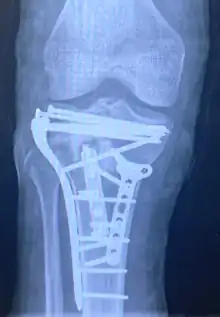

Pain may be managed with NSAIDs, opioids, and splinting.[1][2] In those who are otherwise healthy, treatment is generally by surgery.[1] Occasionally, if the bones are well aligned and the ligaments of the knee are intact, people may be treated without surgery.[2] The surgery usually involves reducing the fractured fragments of the tibia plateau to their anatomical position and fixing them in place with screws only or fixed angle anatomical plates ensuring absolute stability. Implant selection is based on the type of injury. Generally, simple or incomplete fractures (Schatzker type 1) of the plateau are compressed with 6.5mm partially threaded cancellous screws. Complex type fractures will require a plate for enhanced stability. As the tibia condyles articulate with the femur (thigh bone) to form knee joint, any incongruity in the articular surface is unacceptable as it leads to early arthritis. Prolonged immobilization of the knee joint is also not recommended which result in stiffness of the joint and difficult recovery. Following a tibial plateau fracture, the patient is at risk for arthritis. This is referred to as post-traumatic arthritis. The more displaced the joint intra-articular surface is, the more likely post-traumatic arthritis is to occur. This occurs due to injury to the joint surface cartilage. When cartilage is damaged, arthritis can occur.[15] It's currently debated what role primary total knee arthroplasty (Joint Prosthesis) plays in the treatment of tibial plateau fractures. Although accompanied with risks small studies have shown promising results.[16]

Surgery

A tibial plateau fracture requires orthopaedic surgical intervention for treatment. After X-ray and CT scans confirm fracture, Open Reduction Internal Fixation (ORIF) with medial and/or lateral plateau fixation is done. There are 5 different approaches that are most commonly used.[3]

These are: anterolateral, posteromedial, posterolateral, posterior, and dual plate fixation.